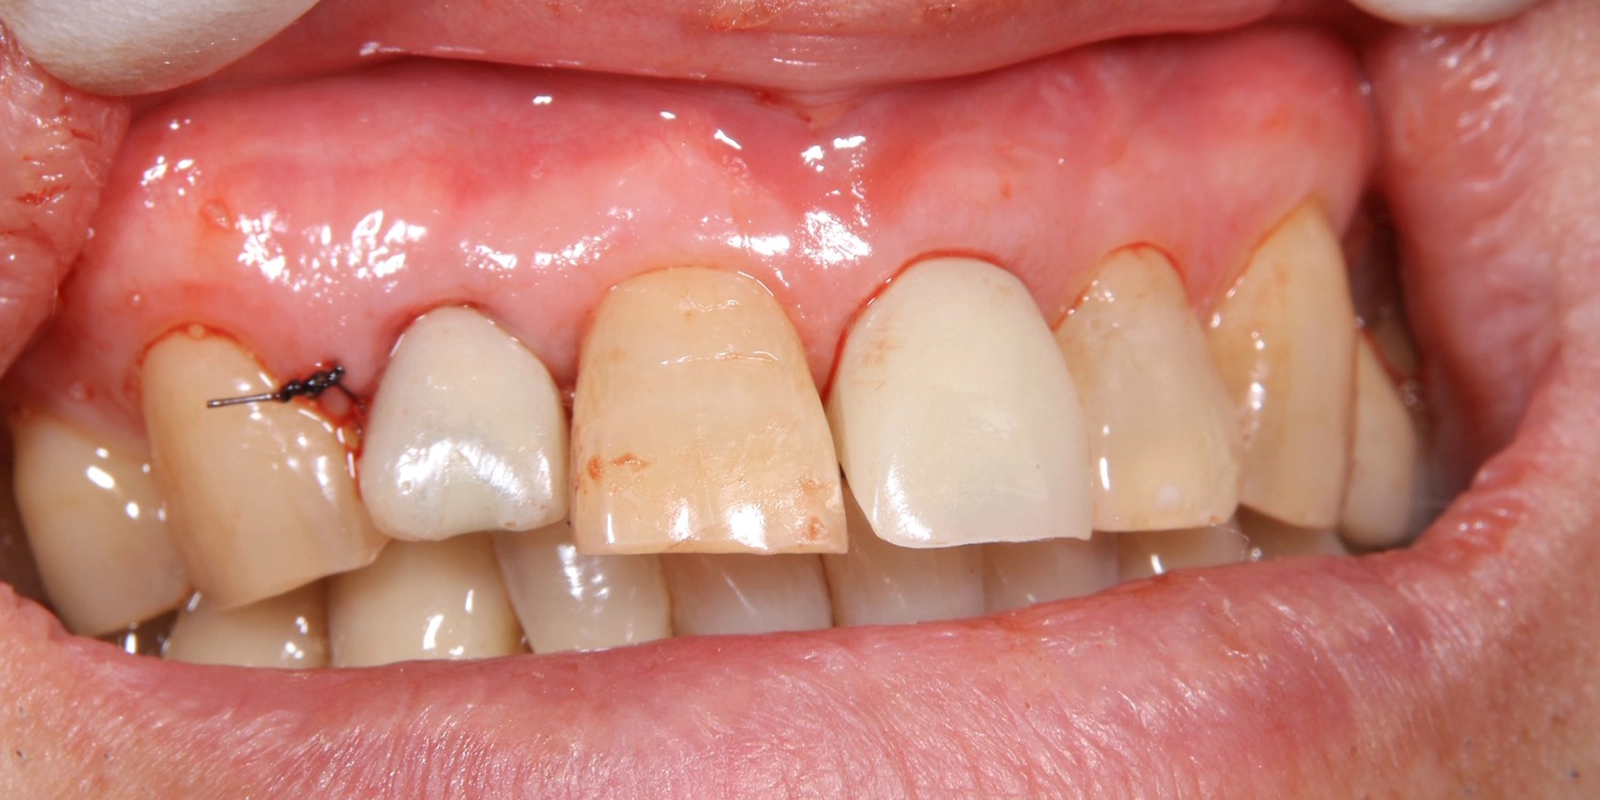

こちらの写真は術後1週間ほど経過した後の様子になりますが、仮歯の状態でも全く問題ございませんでした。

麻酔下で右上2番・左上1番を丁寧に抜歯しました。抜歯後の穴(抜歯窩)は次のステップでインプラントを入れる場所になるため、骨や歯肉へのダメージを最小限に抑えるよう慎重に処置しました。

抜歯した穴をそのまま利用して、チタン製のインプラント(人工歯根)を骨の中に埋め込みました。埋入直後に十分な固定力が得られていることを確認しながら処置を進めました。

インプラント周囲の骨が不足している部分に骨補填材(骨の代わりになる材料)を詰め、骨の再生を促す「GBR(骨再生誘導法)」を同時に行いました。

インプラント埋入後、その日のうちに仮歯を装着しました。前歯がない状態になる期間はありません。